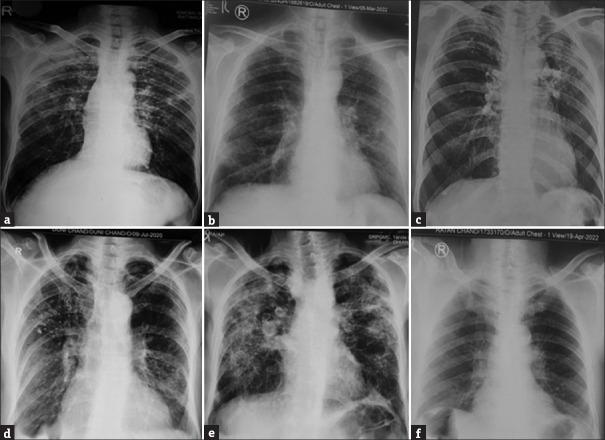

Eight out of twelve patients were having silica exposure in the form of stone cutting, cement exposure, and working with concrete. The average age was 55 ± 10.72 years with average smoking exposure of around 24.4 ± 12.8 pack years. Skin thickening was reported by all patients with an average modified Rodnan score of 18.33/51 in diffuse and 7/51 in limited cutaneous systemic sclerosis. Raynaud's phenomenon and sclerodactyly were universal findings, while 9 (75%) patients had digital pitted scars. Antinuclear antibodies were present in all patients and specific antibodies substantiated the clinical assessment in almost all patients. Interstitial lung disease was the most common systemic finding present in 11 (91%) patients and tuberculosis was diagnosed in 2 (25%) cases with silica exposure. Gastrointestinal and cardiac system involvement was seen in 5 (41.6%) and 4 (33.3%) patients, respectively.

12例患者中有8例有接触二氧化硅的情况,形式包括石材切割、接触水泥以及从事混凝土作业。平均年龄为55±10.72岁,平均吸烟史约为24.4±12.8包年。所有患者均有皮肤增厚,弥漫性皮肤系统性硬化症患者的平均改良Rodnan评分为18.33/51,局限性皮肤系统性硬化症患者为7/51。雷诺现象和指端硬化是普遍存在的表现,9例(75%)患者有指端凹陷性瘢痕。所有患者均存在抗核抗体,几乎所有患者的特异性抗体均证实了临床评估结果。间质性肺病是最常见的系统性表现,11例(91%)患者出现,2例(25%)接触二氧化硅的患者被诊断为肺结核。分别有5例(41.6%)和4例(33.3%)患者出现胃肠道和心脏系统受累。